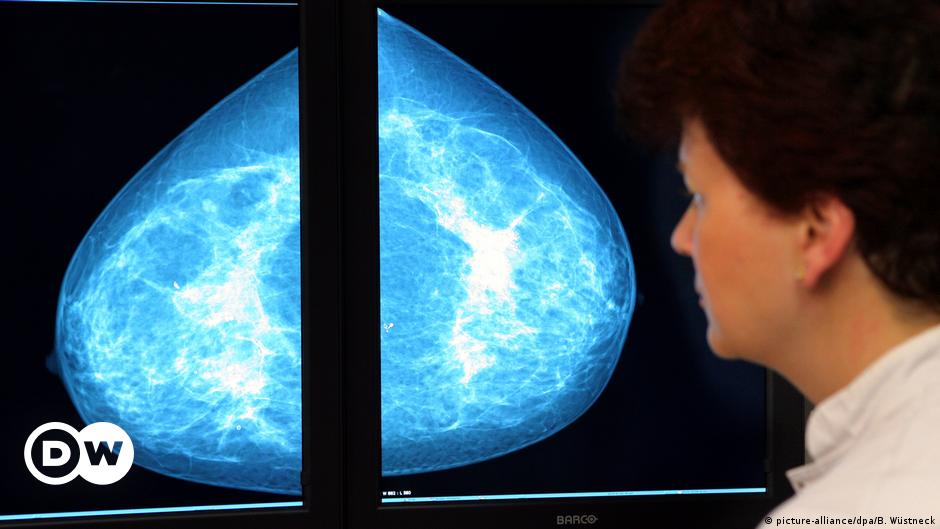

Overweight women produce increasing amounts of female sex hormones in their fat tissue and hence have a higher risk for uterine or breast cancer.

The oral contraceptive pill can increase the risk of breast cancer, but it can also decreases the risk of ovarian cancer. Consult your personal doctor to find out what is best for you.